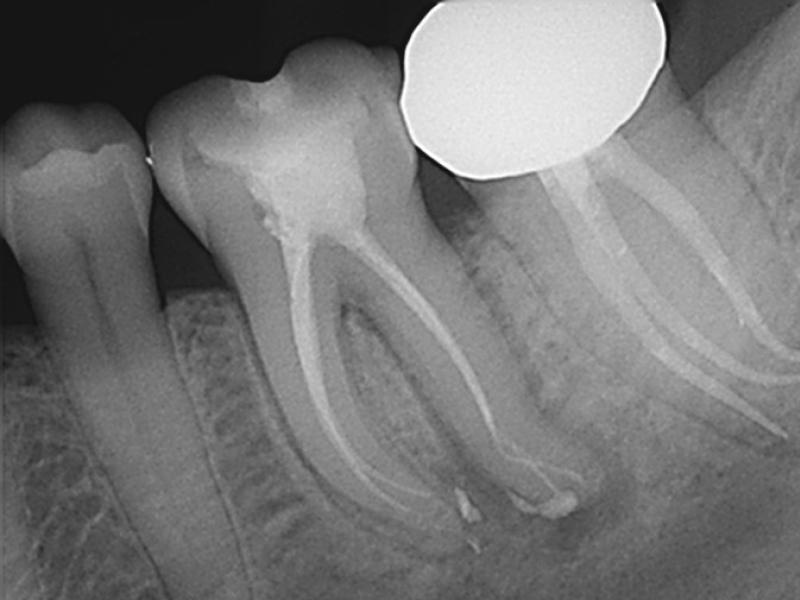

Retreatment with Acute Apical Abscess

GentleWave

®

G4 with ProControl

™

Michael J. Ribera, DMD, MS

View Case Details